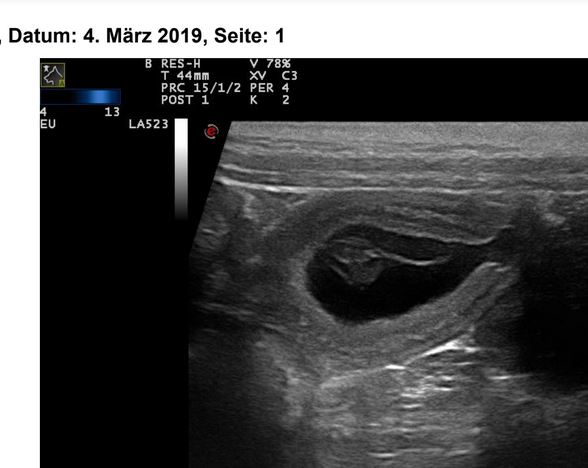

04.03.2019

(24. Trächtigkeitstag)

Der erste große Tag :-):

Percya ist trächtig! Falls alles weiter gut geht, werden um den 12.04.2019 kleine Nightingale's Fellow Schens bei uns einziehen!